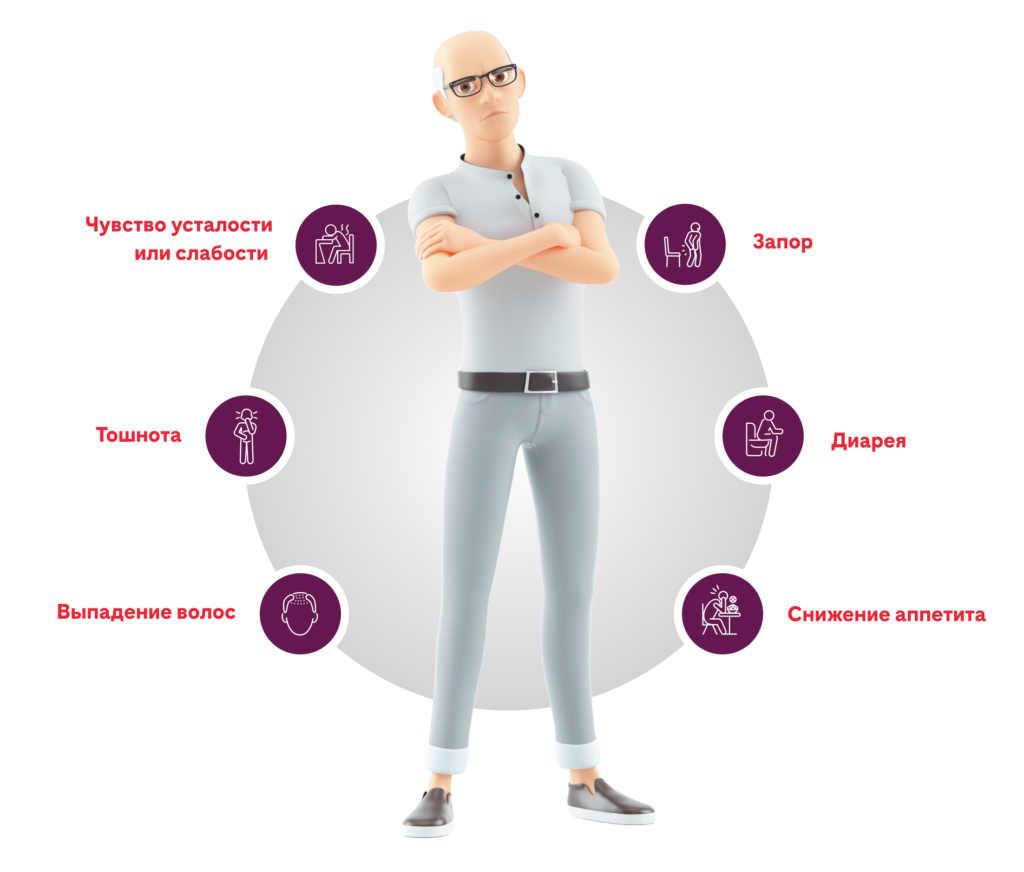

Побочные эффекты, которые могут возникнуть при лечении Атезолизумабом

Наиболее распространенные побочные эффекты при применении Атезолизумаба в комбинации с другими препаратами для лечения рака лёгкого включают: